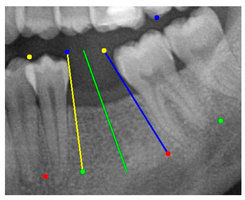

| Comparison with dentist’s ground truth (black line) and our framework (green line) | ||||||

| Validation Image 1–6 | ![]() | ![]() | ![]() | ![]() | ![]() | ![]() |

| MSE | 3.59 | 1.29 | 0.41 | 0.80 | ||